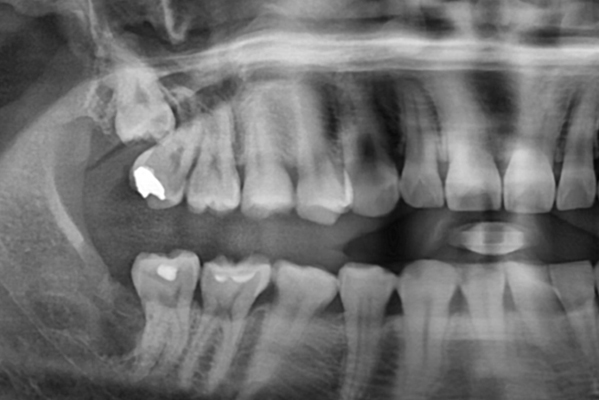

사랑니가 정상적으로 나오지 않고 비정상적인 형태로

나면 참기 힘들 정도의 통증을 동반하는 경우가 많습니다.

이런 경우에는 통증을 줄이기 위하여 사랑니 발치를 진행해야 합니다.

대학병원에서 주로 사용하는 3D CBCT 스캔은 사랑니의 형태, 뿌리 구조는

물론 하치조 신경관의 거리까지 기존 디지털 기기에 비해 3000배 이상

정밀하게 촬영하여 보다 안전한 시술 계획 수립이 가능하게 해줍니다.